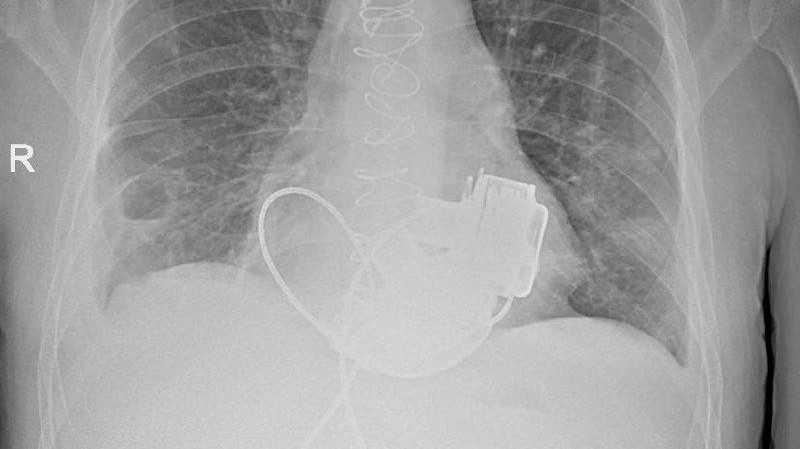

В Мариинской больнице Санкт-Петербурга в конце ноября 2025 года впервые в России имплантировали сразу два искусственных желудочка сердца – левое и правое. Сейчас 36-летний пациент «живет без пульса», но уже готовится к выписке, сообщила пресс-служба городского Комитета по здравоохранению.

Врачи приняли решение о проведении имплантации искусственных желудочков. Обычно пациенту вживляют одно такое устройство, в этом случае потребовались сразу два прибора. Операцию провела бригада хирургов под руководством главного внештатного специалиста по сердечно-сосудистой хирургии Комздрава академика РАН Геннадия Хубулавы. Она продолжалась около четырех часов, самым сложным было синхронизировать работу двух искусственных желудочков сердца.

Сегодня пациент уже научился жить с двумя приборами в теле, несмотря на непростой послеоперационный период. В Комздраве назвали имплантацию искусственных желудочков «мостиком» к трансплантации сердца.